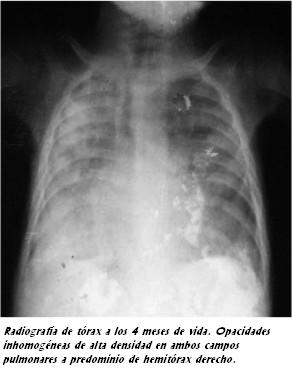

Paciente de 7 años, sexo femenino, procedente de Rivera, de medio socioeconómico deficitario. De sus antecedentes se destacaba a los 4 meses de vida una infección respiratoria grave que requirió asistencia ventilatoria mecánica por 14 días y episodios de crisis broncoobstructivas leves recurrentes con períodos intercríticos asintomáticos (figura 1). Presentaba un buen crecimiento y desarrollo e inmunizaciones correspondientes a su edad vigentes. No había antecedentes familiares patológicos ni consanguinidad y de los antecedentes ambientales destacaba la exposición pasiva a humo de tabaco.

El hallazgo característico en la radiografía de tórax consiste en cambios difusos micronodulares finos distribuidos en ambos pulmones, sobre todo en los dos tercios inferiores, descrito en la literatura como infiltrado en tormenta de arena (7,9).